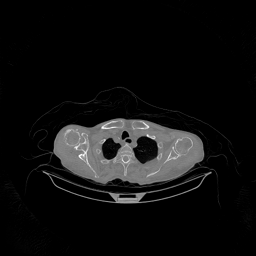

The results for simulated noisy data are shown in Fig. 2. The first and third rows display two representative slices from the test set, and the second and fourth rows present the corresponding error maps. The traditional WCE method suppresses cupping artifacts and recovers some missing anatomical structures but still shows noticeable deviations from the ground truth. Predictions from the four diffusion-based models demonstrate a markedly improved ability to restore anatomical structures. Among them, cDDPM fails to fully reconstruct the patient bed and retains residual noise in its outputs. This noise is attributable to an incomplete reverse denoising process rather than residual Poisson noise, as evidenced in our noise-free experiments (Fig. 5 in the Appendix). PatchDiffusion, diffusionGAN, and I2SB achieve similar visual quality, with I2SB producing the cleanest and most consistent reconstructions.

Quantitative results in Tab. V further confirm I2SB’s superiority over conventional deep learning methods such as FBPConvNet and Pix2pixGAN across RMSE, PSNR, and SSIM. Compared to other diffusion models—including cDDPM, PatchDiffusion, and cLDM—I2SB delivers higher image quality, while diffusionGAN achieves comparable quantitative performance. However, I2SB demonstrates a significant advantage in inference efficiency, as summarized in Tab. IV.